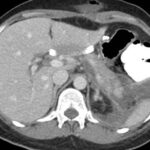

Caso 2

Paciente femenina de 48 años de edad que ingresa a Hospital Sanatorio Franchin por síntomas de cefalea y mareos, cuadro que se hace progresivo, presentando síncopes y posteriormente alteración del estado de conciencia. Los exámenes clínicos revelan una glucosa de 40 mg/dl, concomitante con insulina alta y péptido C elevado. Ingresa de forma programada para realización de duodeno pancreatectomía el 29 de mayo de 2021. Imágenes diagnósticas muestran estudio trifásico de tomografía de abdomen, lesión nodular en la cabeza del páncreas con ávido realce en fase arterial que en resonancia magnética se observa hiperintensa en T2, presenta restricción con la difusión y caída de la señal en el ADC. Además presenta realce tras la administración de contraste con gadolinio.

Estudio histopatológico reveló tumor neuroendocrino bien diferenciado grado 1.